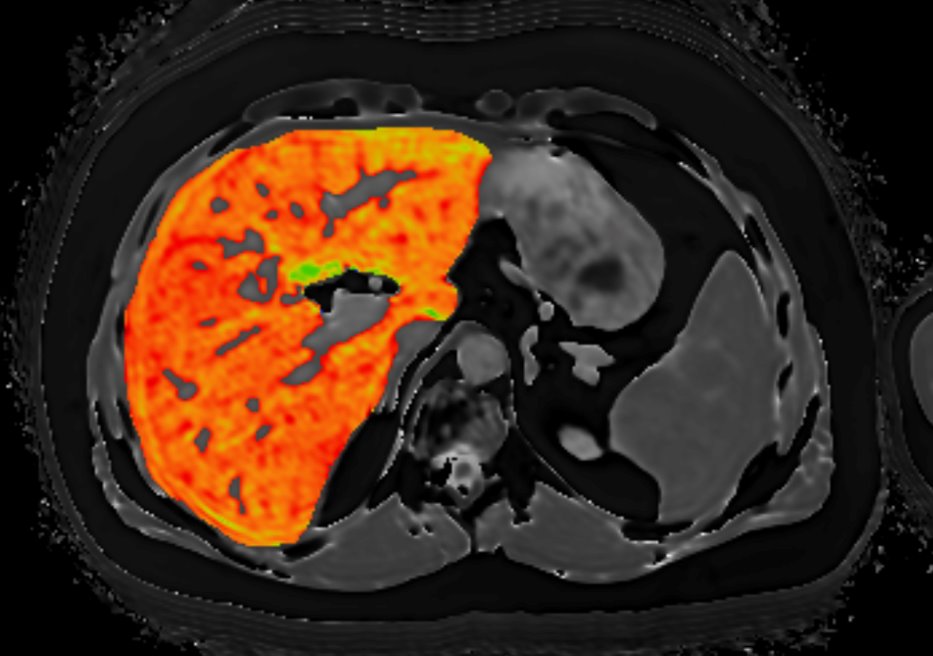

At present, the gold standard for diagnosing and staging liver disease is liver biopsy, which is costly, invasive, and carries risk for the patient. For these reasons, clinicians are reluctant to use it for people suspected of having NAFLD/NASH or for serial assessment for disease monitoring. Perspectum Ltd has developed LiverMultiScan®, a novel, non-invasive, quantitative Magnetic Resonance Imaging (MRI) post-processing software tool that has demonstrated high diagnostic accuracy for the early assessment of liver disease (Banerjee et al, 2014; Pavlides et al, 2016; Pavlides et al, 2017). This technology has the potential to improve the care pathway for patients with suspected NAFLD, by reducing the number of visits and unnecessary liver biopsies. Perspectum was awarded a Horizon 2020 grant by the European Commission, Executive Agency for Small and Medium-sized Enterprises (EASME) to develop the health economic case for LiverMultiScan as part of the diagnostic pathway in European healthcare settings. This project is known as RADIcAL.

Segmented liver using LiverMultiScan software